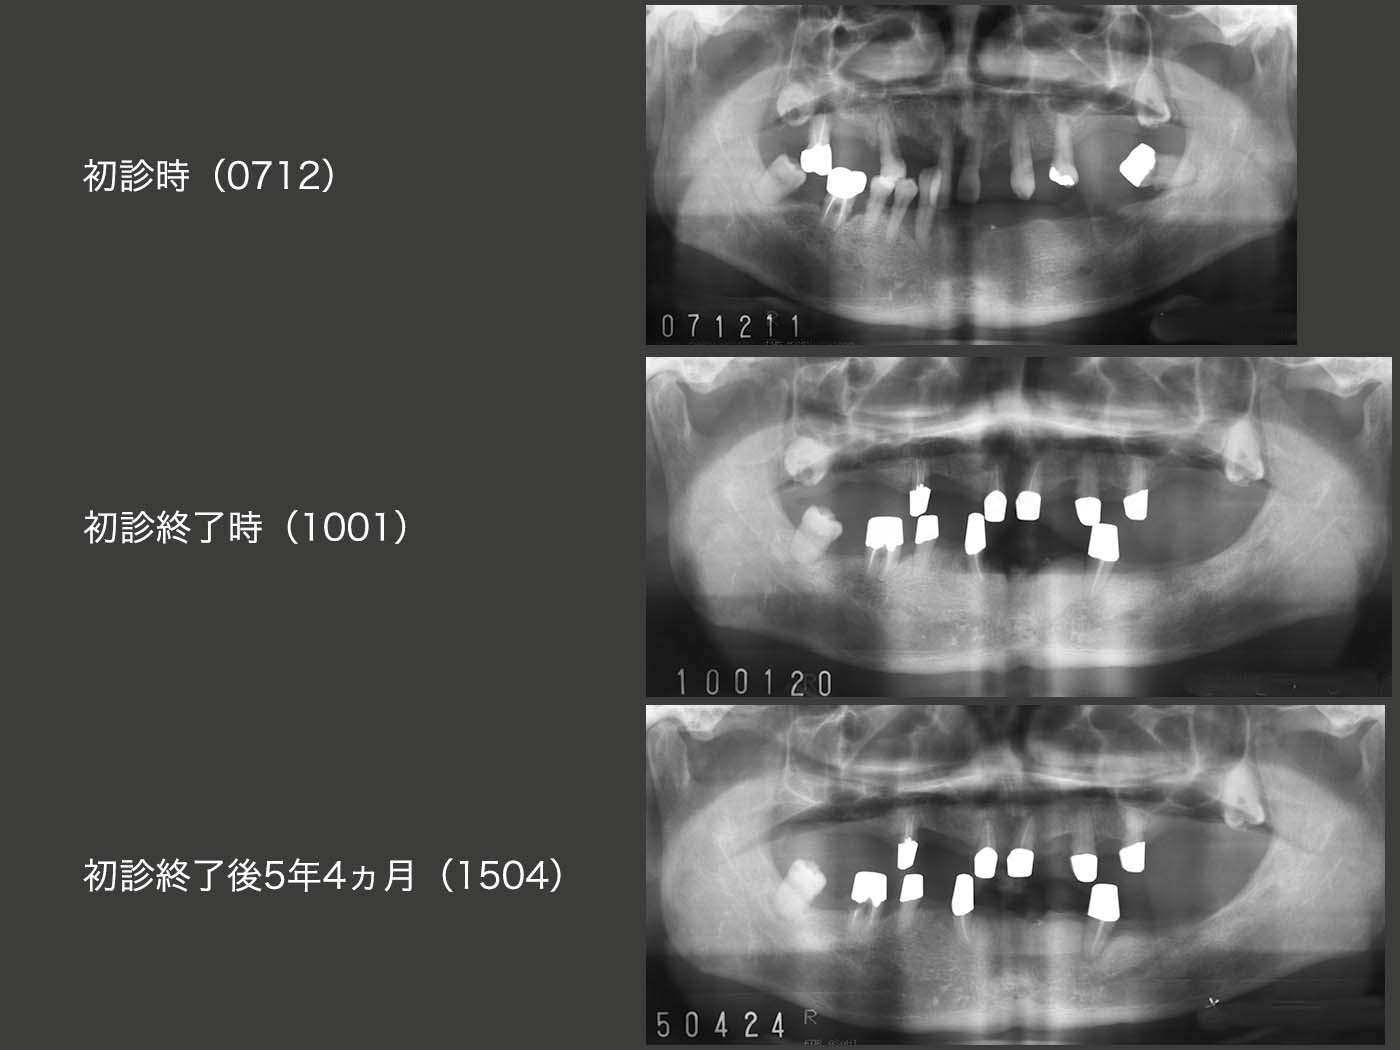

2007年12月初診,67歳男性.義歯が合わないとのことで来院.右側の小臼歯部のみに咬合支持があり,全体に歯周病が進行していた.著しく歯の動揺が大きい右上7および左下8は保存不可能であった.まず義歯の調整,つぎにプラークコントロールの徹底と歯周基本治療に専念した.患者さんはとても穏やかな人で,治療にも大変協力的で歯周ポケットは改善傾向を示した.

先に上顎のコーヌス義歯を製作した.つぎに下顎の義歯に取りかかったが,左下に歯がないためどうしても右咬みになっているのを何とか改善したいと考えた.最初左下にインプラントを1本植立したが,私の手技の稚拙のため生着しなかった.そこで,右下には歯が5本あることから,対合歯との接触が少なく,また抜歯しやすい小臼歯の右下4をドナー歯に選定し,2009年6月,左側に移植した.

下に示すスライドは,10年1月初診終了時の状態である.歯周ポケットは右下6を除いて3mm以下に改善した.

コーヌス義歯は順調に推移していたが,2014年頃から異変が生じた.下顎義歯の取り外しがきつくなったため,1ヵ月間,下顎義歯を外さなかったとのことであった.その時はひょっとしてアルツハイマー病の初期ではないかと疑ったが,どうすることもできずそのままになってしまった.その後,症状は経過観察のたびに進行していった.16年になると,奥様に付き添われて来院するようになったが,プラークコントロールもどんどん悪化していった.もうセルフコントロールは無理であったため,奥様にブラッシングしていただくようにお願いした.しかし,16年7月,奥様も疲労困憊といった具合で,下の世話もあり,とても口の中の清掃までは無理と宣告されてしまった.患者さんは遠方からの通院であり,近くでクリーニングをしてくれる歯科医あるいは在宅介護を利用してもらう方が好ましいと考え,そのように説明した.もちろん義歯に関しては私が責任もつと伝えたが,その後連絡はない.患者さんも奥様も本当に良い人で,こちらは何もしてあげられないことに困惑を感じざるを得ない.もう一度,患者さんにお目にかかりたい.